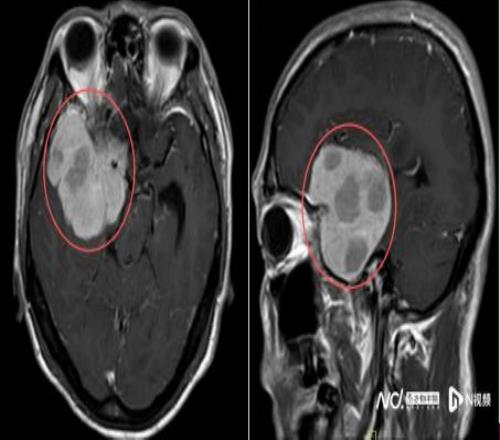

2025年10月起,他在跑步途中频繁在转弯处摔倒,偶尔还感觉一侧手脚乏力,起初并未放在心上。但随着摔跤次数不断增多,又无明显诱因地出现持续一周的头痛,他和家人终于警觉起来。同年11月中旬,陈叔家人带他在当地医院做了一次检查。MR结果如晴天霹雳:右额颞部蝶骨嵴占位病变,大小约5.5x6.6x5.8cm,考虑脑膜瘤。

鉴于肿瘤体积巨大、位置较深,考虑为右侧额颞蝶骨嵴内侧型巨大脑膜瘤,肿瘤突入垂体窝和斜坡,环绕颈内动脉及分支、视神经等重要结构,压迫脑干。手术难度是神经外科最复杂的手术之一,犹如刀尖上行走,且已出现进行性神经功能缺损症状:肢体乏力,视力受损,视物重影等,病情复杂、手术风险极高。

专家们一致认为,若不及时干预,肿瘤可能进一步压迫脑组织,导致偏瘫、失明甚至危及生命;而手术虽极具挑战——肿瘤所处位置特别危险,它被视神经和给大脑供血的大血管紧紧环绕,后面还靠近调控呼吸、心跳的“生命中枢”脑干——但却是目前最有效的治疗手段。